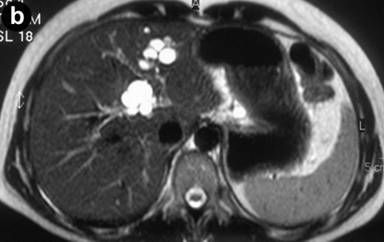

Caroli syndrome is characterized by problems in the liver parenchyma and bile ducts. This is a rare genetic condition that results in congenital hepatic fibrosis that can result in portal hypertension and dilatation of the intrahepatic bile ducts that predisposes to bile duct stone formation and resultant obstructive jaundice. Text Reference: https://rarediseases.org/rare-diseases/caroli-disease/ Image Source: https://en.m.wikipedia.org/wiki/Caroli_disease